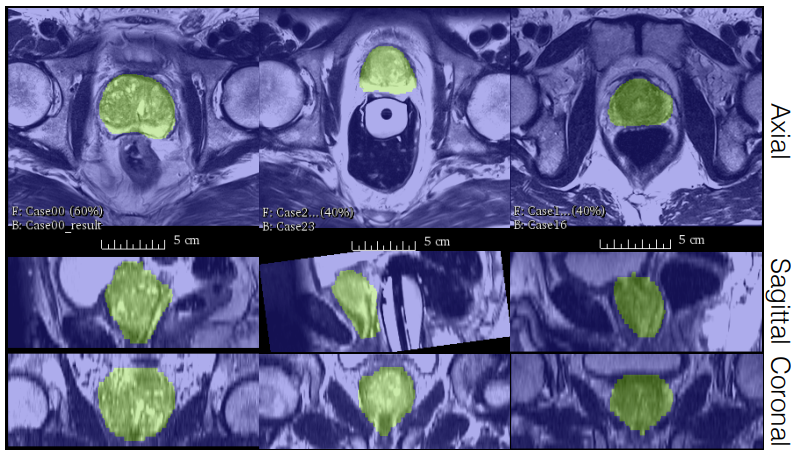

Fig 1. Image segmentation results on prostate MRI scans from the PROMISE 2012 dataset [3].

V-Net was trained on a dataset of prostate scans in MRI. Since there aren’t many annotated medical images available for training, the model was also trained on deformed versions of the training dataset.

The trained model, V-Net, performs the image segmentation tasks on the dataset with a higher accuracy and less processing time than previous methods. The results can be seen in the table below where V-Net with Dice loss has the highest score.